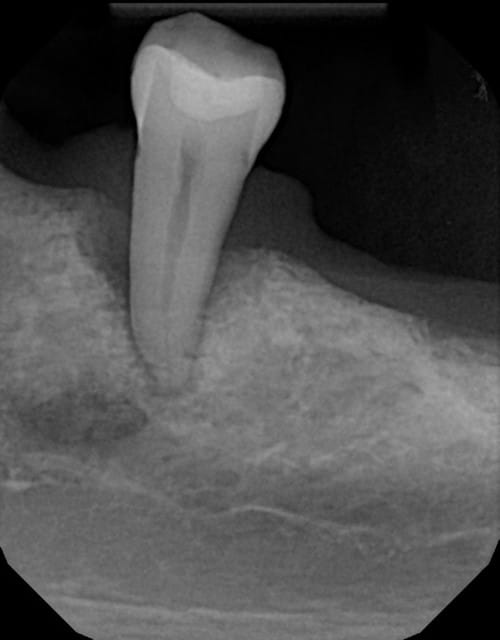

Sur le sujet paro

Ce patient est dans cet état depuis des années...

Soins de base, ne porte pas de stellite (n'en veux pas)

Cinquantaine, fumeur, paro marginale chronique(inflamation au Dilantin), aucune mobilité notable...et voilà, en 6 mois, cette dent passe à une mobilité de 3 +.

J'enlève ou je tente quelque chose ?

Pas de sous pour des implants en passant...mais de toute façon, fumeur et implants dans un cas comme celui-ci, je fais pas

--